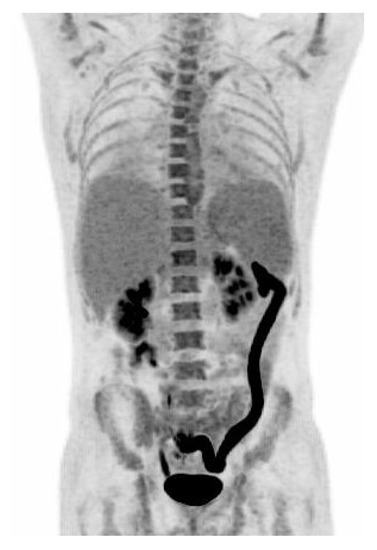

Figure 1.

A 33 year-old man with known inflammatory bowel disease (IBD), on azathioprin (Imurel®) and mesalazin (Asacol®) treatment, presented with two weeks of hyperpyrexia up to 40.6 °C, dry cough, and water like diarrhoea which—unlike usual IBD—contained only a limited amount of blood. One month earlier, the patient had been travelling for 17 days in Jamaica. The patient was initially treated as an outpatient with roxithromycin for suspected pneumonia with no effect, and was admitted to the hospital after 10 days with symptoms. At admission, we found elevated C-Reactive Protein (CRP) 58 mg/L (normal range <10 mg/L), Alanine aminotransferase (ALAT) 217 U/L (normal range 10–70 U/L), Lactate dehydrogenase (LDH) 778 U/L (normal range 105–205 U/L), and Ferritin 2,560 µg/L (normal range 12–300 µg/L). Hemoglobin was low 6.5 mmol/L (normal range 8.3–9.5 mmol/L). White blood cell count was within normal range; 6.1 × 109/L (normal range 3.5–8.8 ×109/L). Blood cultures were negative. Human immunodeficiency (HIV) test was negative, hepatitis panels were either negative or consistent with previous vaccination. Dengue IgG and IgM, Zikavirus IgG and IgM and DNA, Chikungunya IgG and IgM and Malaria microscopy were all negative. A stool sample tested negative for bacteria, vira, and parasites. X-ray of the thorax was normal. CT of the abdomen revealed an enlarged descending colon with oedema of the colon mucosa and splenomegaly. The patient did not improve, and due to persistent pyrexia and watery diarrhoea, elevated ALAT and the finding of an enlarged spleen; Epstein Barr virus (EBV) and Cytomegalovirus (CMV) testing were ordered, especially as CMV reactivation have been found to be associated with IBD flare-up in patients on immunosupressive therapy. EBV serology was consistent with a previous infection; EBV DNA in the blood was negative. Specific CMV IgM antibodies were detected, and CMV IgG antibodies were borderline. However, only 3,000 copies/mL of CMV in the plasma were detected by PCR. At day 10 after admission, an 18F-FDG PET/CT scan was performed to identify the cause of fever of unknown origin (Figure 1). The scan revealed pathologically high 18F-FDG uptake in the left side of the colon, and mild diffuse increased activity in the bone marrow and in the enlarged spleen (16.5 cm). The intense 18F-FDG uptake in the left side of the colon was consistent with either flare-up in IBD or an infectious colitis. CMV testing was repeated on day 8 after admission, and this time both CMV IgG and IgM antibodies were detected, indicating a CMV IgG seroconversion consistent with a primary CMV infection. A sigmoidoscopy revealed inflammation with oedema and submucosal bleeding from 45 to 70 cm from the anus, which is not characteristic for IBD. The biopsy specimen from the colonic lesions did not reveal cells with CMV inclusion bodies, but PCR of the biopsies from the intestinal mucosa were positive for CMV DNA with 12,000 copies/mL suggesting compartmentalization of CMV manifestation. The patient was treated with ganciclovir 5 mg/kg twice daily for 14 days with good clinical response. Following treatment, CMV DNA in the blood was undetectable. CMV colitis is a known, but relatively rare complication to CMV infection that is observed in severely immunocompromised patients including those who have HIV and IBD, or have received an organ transplantation, chemotherapy, or other immunosuppressives [1,2,3]. CMV colitis as a complication in patients with IBD has been associated with active disease, immunosuppressive medication, steroid treatment, and especially steroid refractory disease progression [4]. Diagnosing CMV colitis is based on clinical symptoms, biochemical findings, typical endoscopic findings, histological examination of biopsies from colon mucosa, and detection of CMV DNA in the blood and biopsies from affected colon mucosa [1,2,3,4,5,6]. Discrimnation between activity in IBD and an acute CMV infectious colitis is difficult, but of great importance in order to initiate antiviral therapy. IBD patients with colitis and systemic signs of inflammation, steroid-refractory disease, pyrexia, splenomegaly, and a lack of leukocytosis have a high pre-test probability for CMV colitis [6] as was the case in our patient. 18F-FDG PET/CT has been shown to have a potential for a noninvasive whole-body assessment of IBD, with FDG accumulating along the intestinal tract including assessment of disease extent, activity, and treatment response [7]. In the present case, PET/CT scan revealed pathologically high 18F-FDG uptake in the left side of the colon, and mild diffuse increased activity in the bone marrow and in the enlarged spleen. The initial blood samples and the sigmoideoscopy did not indicate activity in the patients IBD, and the patient was diagnosed with a primary CMV colitis, based on CMV seroconversion and CMV DNA in the blood and the biopsy from the colon. The changes revealed by the PET/CT were consistent with an acute infectious colitis. Only one case of 18F-FDG uptake in acute CMV colitis has been previously reported [8]. This case highlights that a positive 18F-FDG PET/CT scan of the colon can be due to CMV colitis.